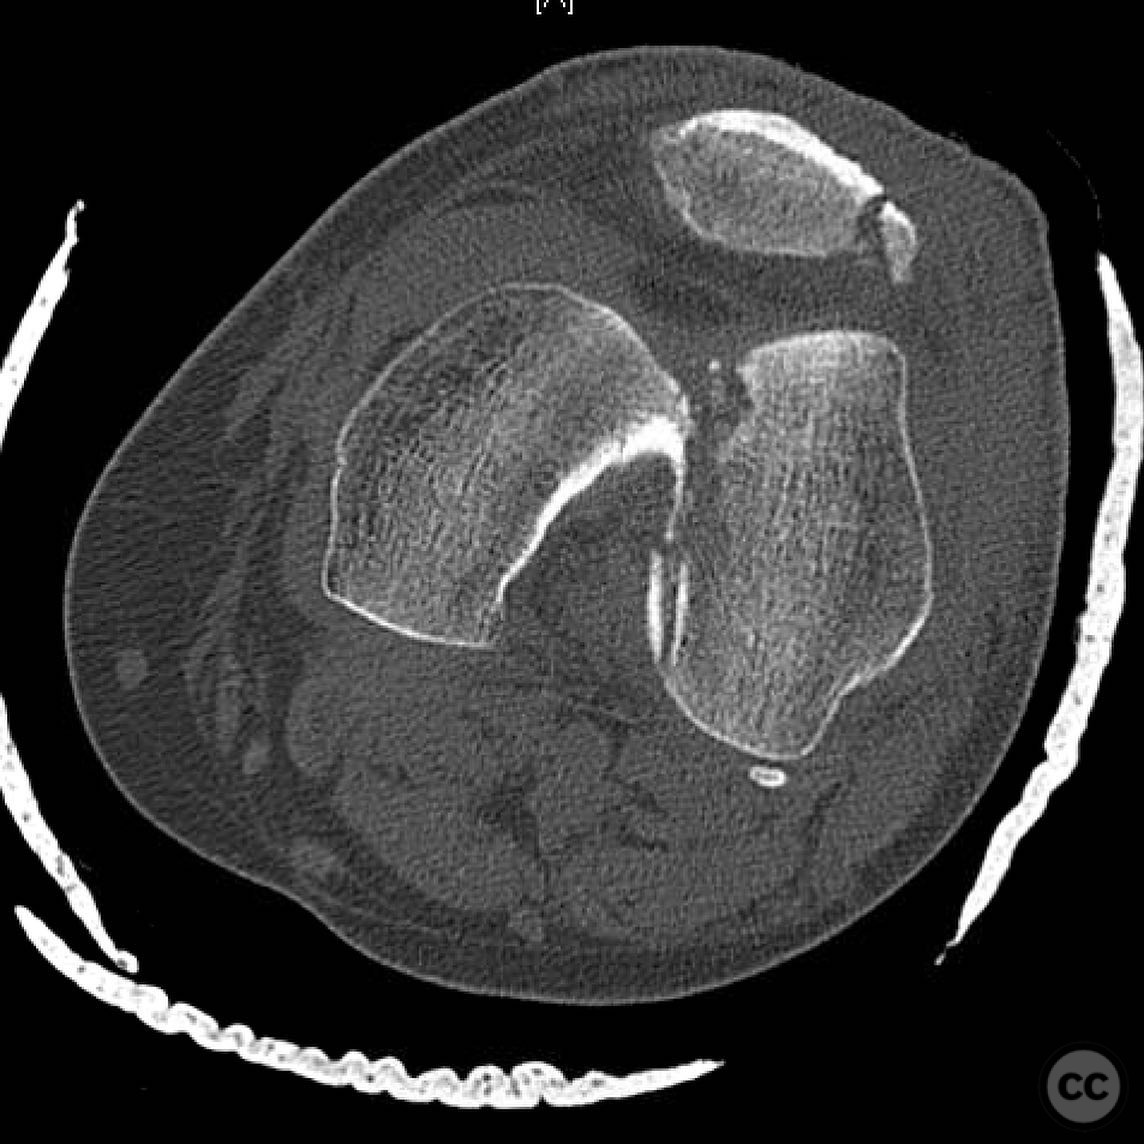

Clinical and radiological findings:  A 44-year-old male cyclist was involved in a collision with a car, resulting in open fractures of the distal femur and segmental tibia. The femoral fracture presented with a 4 cm transverse wound on the anterior aspect, while the tibial fracture had a 2 cm anterolateral wound at the distal site. There were no associated head, chest, or abdominal injuries, and compartment syndrome was not present. Vascular examination was unremarkable.

Anatomical surgical approach:  For the tibia, a longitudinal incision was made to access the proximal tibial start site for intramedullary nailing. Percutaneous clamps were utilized for reduction, supplemented by blocking screws as needed. For the distal femur, an external fixator was applied initially, followed by an in situ lateral approach for plating after reduction was achieved.

The tibial nailing required precise identification of the start site under fluoroscopic guidance, with percutaneous clamps aiding in reduction. Blocking screws were considered but not necessary due to successful reduction with clamps alone. The distal femur presented challenges in achieving coronal and sagittal alignment, necessitating reliance on the external fixator for reduction before proceeding with plating.